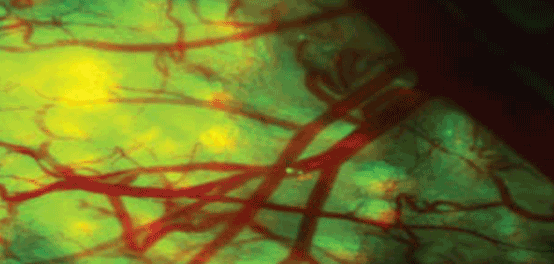

MICROSCOPY: Off-the-shelf components enable a new generation of confocal microscopy